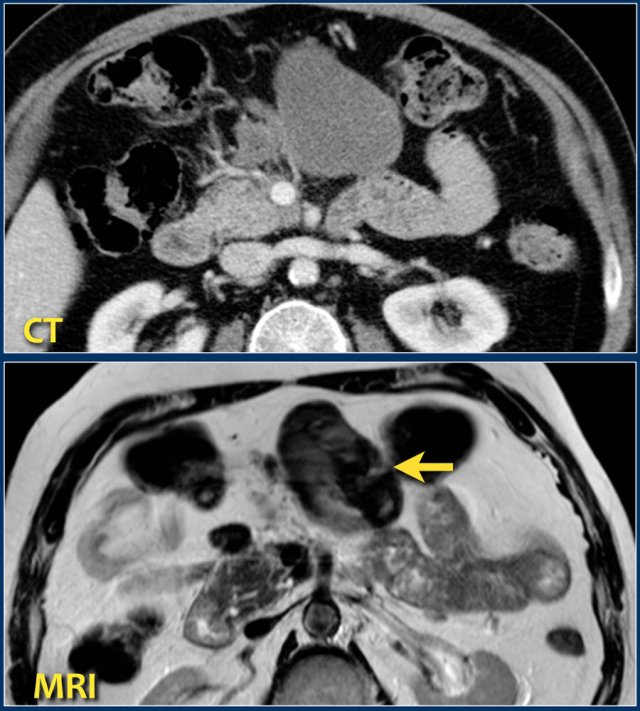

MRI

MRI is superior to CT in differentiating between fluid and solid necrotic debris.

Here a patient with several homogeneous peripancreatic collections on CT.

These collections also show homogeneous high signal intensity on a fat-suppressed T2-weighted MRI image, are fully encapsulated and contain clear fluid (i.e. pseudocysts).

This patient had an acute necrotizing pancreatitis with onset 2 months earlier.

The CT-image shows a homogeneous peripancreatic collection in the transverse mesocolon (arrow).

A T2-weighted MRI sequence shows that the collection has a low signal intensity (arrow).

Most likely this is necrotic fat tissue (i.e. sterile necrosis or walled-off necrosis).

This patient had no fever or signs of sepsis.

Endoscopic or percutaneous drainage would have little or no effect on its size, but increases the risk of infection.